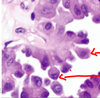

multinucleated squamous cells containing eosinophilic to basophilic viral inclusions with a “ground-glass” appearance

The cell in the center shows HSV cytopathic effect